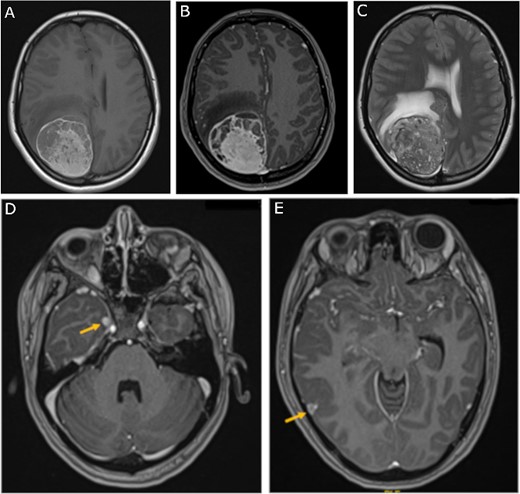

The patient underwent a right parieto-occipital craniotomy and gross total resection of the mass. Histological sections (Fig. 3A and B) showed a heavily pigmented cellular neoplasm with spindled to oval tumor cells with limited cytologic atypia and mitotic count under 0.5 mitoses/mm2, distinguishing it from malignant melanoma. There was no evidence of brain invasion. Immunohistochemistry was positive for Melan A (Fig. 3C) and HMB45 (data not shown). Cellular proliferation was assessed by staining for Ki-67, which was positive in <2% of tumor cells. Solid tumor next-generation sequencing identified the pathogenic GNAQ mutation pQ209P. The histologic, immunohistochemical, and molecular findings were consistent with meningeal melanocytoma.

Tumor histopathology and immunohistochemical analysis; (A, B) hematoxylin and eosin-stained sections of heavily pigmented cellular neoplasm with spindled to oval tumor cells with limited cytologic atypia and mitotic count under 0.5 mitoses/mm2; (C) immunohistochemistry was positive for Melan A; red color represents MelanA immunopositivity; magnification: 3A: 100×, 3B and 3C: 200×.